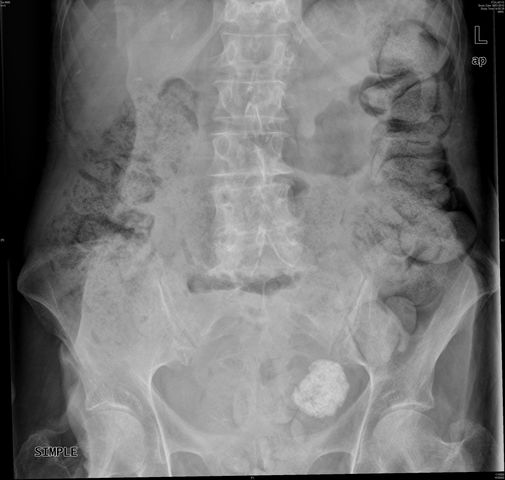

Fecolitos en placa de abdomen.